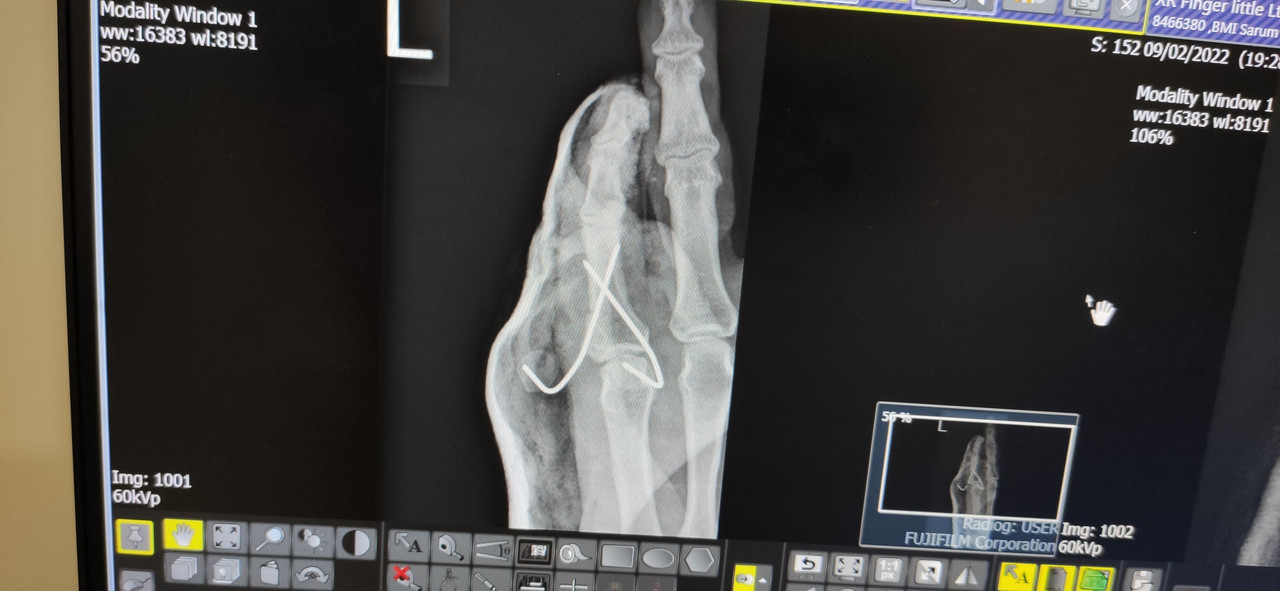

From this

To this

This wasn't good enough for me

So now like this until they pull the K Wires out on Wednesdsay